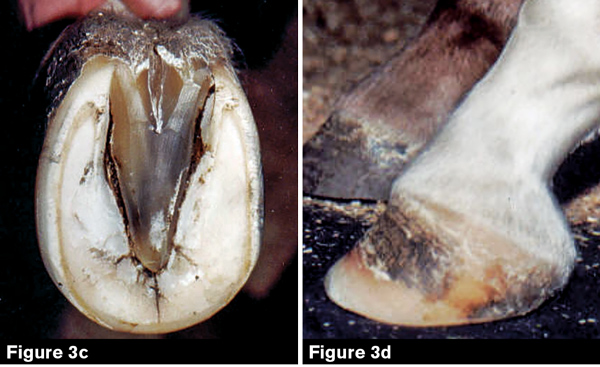

Horses can develop club feet as a result of genetics (Figure 1 see above), Butler says, and the condition might or might not be evident at birth. John Foster Lasley, PhD and author of Genetic Principles in Horse Breeding, discovered that the gene for club feet is recessive, meaning that both sire and dam must have the gene in order for it to be passed along to the foal. The chances are one in four that the foal will receive the gene.